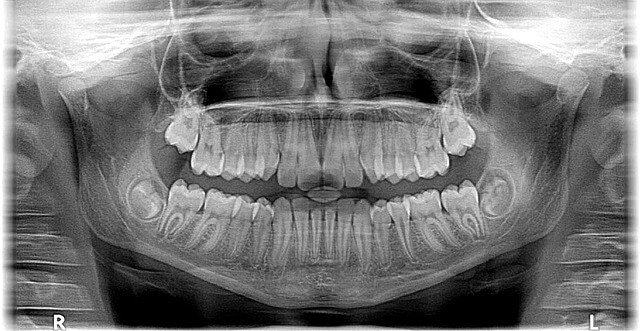

앞니는 ‘보여지는 치아’, 어금니는 ‘씹는 치아’

- 앞니(1~3번 치아)

→ 주로 심미성과 발음 기능

→ 웃을 때 드러나는 부위 → 외관이 매우 중요

→ 치아 뿌리가 가늘고, 뼈가 얇아 시술이 섬세함 - 어금니(4~8번 치아)

→ 씹는 힘을 담당하는 핵심 치아

→ 씹는 면적이 넓고, 치근이 굵고 깊음

→ 치아 하나가 여러 개 역할을 함 → 부하가 큼